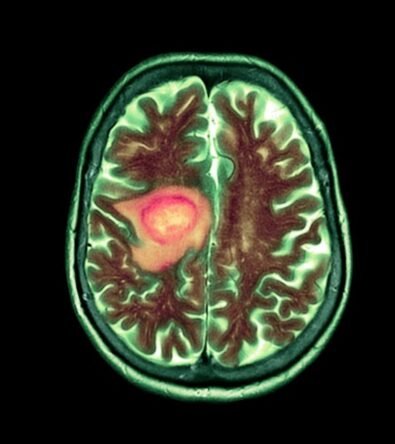

Vorasidenib Under Fire: Experts Question Efficacy and Ethics of New Brain Tumor Drug

Vorasidenib, a new brain tumor drug, faces scrutiny over its efficacy and ethical concerns, raising questions about its real impact on glioma treatment...